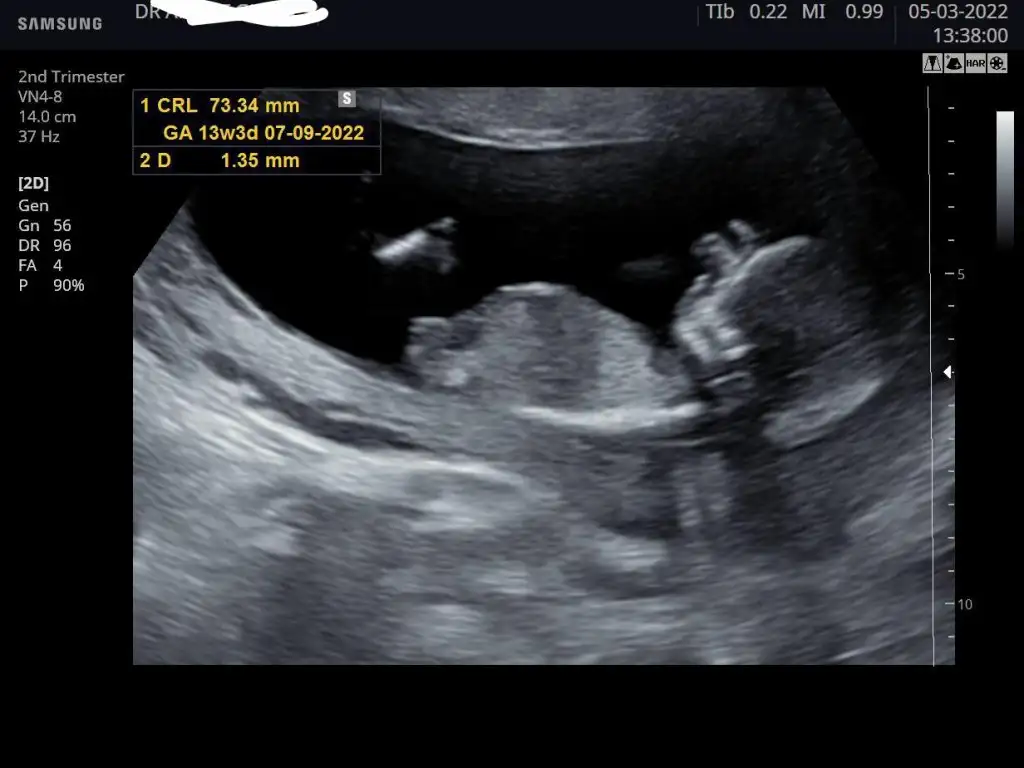

13 haftalık işte ama dedi değişebilir Yani nasip ikili test verdim bakalım inşallah bir sorunu yoktur. Ama benim kese fasulye seninki yuvarlak belli seninki kesin kız benimde kesin erkek tabi Allah bilirde

Canım ben geldim suanlik sıkıntı görünmüyor ense 1.04 çıktı hadi inşallah senden de güzel haberler alalimm

Bende geldım sıkıntı gorunmuyor dedi Dr NT 0,8 mm benimde.